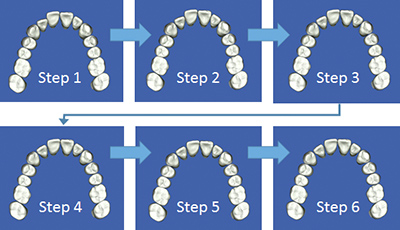

あなたのお口の中の3Dモデルを作成し、それを元に治療計画を立てます。そしてマウスピース型の矯正装置をこのように段階的に設計していきます。

矯正治療をご希望のすべての方には、治療結果の歯列をモニター上で確認できる「outcome simulator(アウトカムシミュレーター)」をお受け頂けるなど、より患者様に分かりやすい治療のご提案をしています。

日本橋はやし矯正歯科では、3Dデジタル矯正システムを応用した

マウスピース矯正での治療が可能となりました。